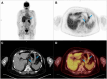

Gastric Metastases From Invasive Breast Lobular Carcinoma, Identified by [18F]FDG PET/CT, 20 Years After Primary Diagnosis: A Case Report

Invasive lobular carcinoma (ILC) of the breast is a rare subtype of breast cancer with distinct metastatic patterns. Although gastrointestinal metastases are rare, they can occur years after initial treatment. This case highlights the diagnostic challenges and management of late-onset gastric metastases. A 68-year-old woman with a history of ILC treated 20 years earlier presented with elevated tumor markers. [18F]fluorodeoxyglucose positron emission tomography/computed tomography (FDG PET/CT) revealed hypermetabolic lesions in the stomach and esophagus in this patient with previously diagnosed gastritis and gastroesophageal reflux disease. Endoscopy and biopsies confirmed the presence of metastatic ILC in the stomach. Adjustment of treatment, including exemestane and everolimus, followed by paclitaxel and tamoxifen, resulted in partial disease control. Late-onset gastrointestinal metastases of ILC are uncommon and require special vigilance, particularly in patients with associated benign gastrointestinal pathologies, which may delay diagnosis. Persistent or new-onset gastrointestinal symptoms in breast cancer patients warrant thorough evaluation, including FDG PET/CT imaging and histological confirmation.